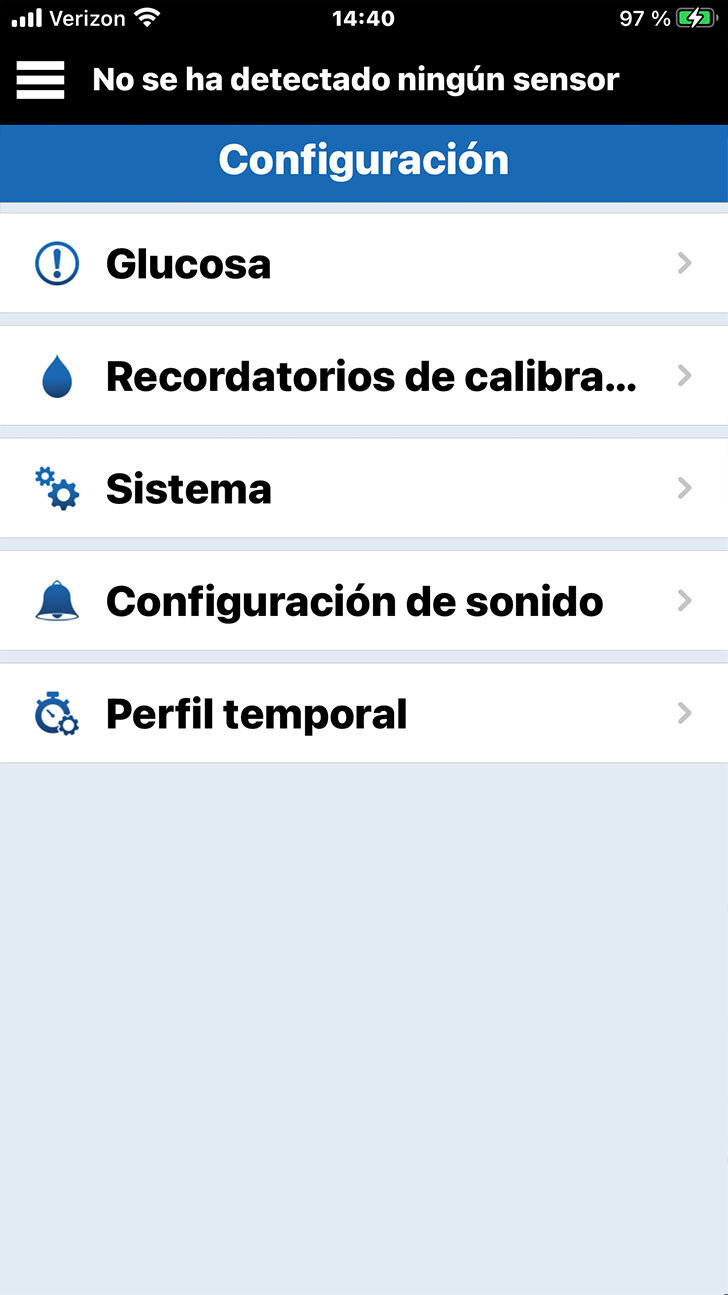

Desplácese hacia abajo y toque Configuración.

A continuación, toque Glucosa.

Desplácese hacia abajo y toque Configuración.

Otra forma importante en la que puede personalizar su sistema de MCG Eversense® E3

OTRAS CONFIGURACIONES

A continuación, toque Configuración

Después elija Configuración de sonido.